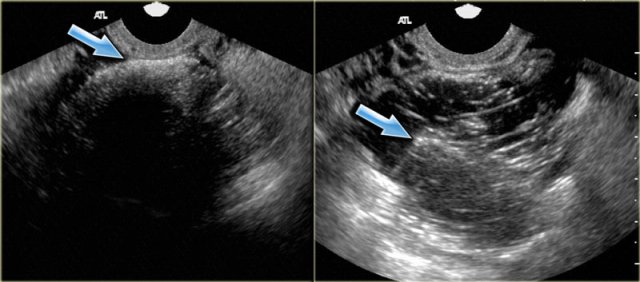

Simple cyst

US findings that allow a confident diagnosis of a simple ovarian cyst are:

- Anechoic lesion with posterior acoustic enhancement

- Unilocular

- Thin, smooth walls

- No solid or well-vascularized components

The US-image shows two simple cysts in the right ovary with ovarian stroma in between.

The surrounding vessels are normal and there are no vascularized septations.

These were simple follicular cysts in a premenopausal woman.